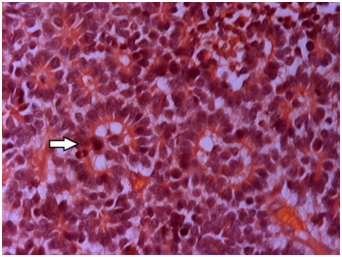

Transparent crystalline lens was separately examined and showed neovascularisation (Figure 2a-d). Enucleated eye ball showed tumour occupying almost entire vitreous cavity. Crystalline lens was seen separately which looked slight yellow and transparent. Three blood vessels were seen in the lens in the peripheral edge and were documented under background illumination. Portion of the lens was again dissected and haematoxyline & eosin (H&E) stain was carried out and it revealed regressed blood vessels in the cross section. Haematoxylin was put on the slide for 10-15 minutes followed by a wash in the running water, then one dip is made in 1% acid alcohol, slide was washed followed by addition of 0.4 % of ammonia for 1 minute. Third wash was made. Eosin was put on the slide for 1 minute and further washing is carried out. Xylene was added. Slide was dried and mounted for microscopic viewing. Study of the specimen in H&E stain showed normal cornea with focal iris neovascularisation. An endophytic tumor was seen in the vitreous cavity with numerous Flexner Wintersteiner (FW), Homer Wright (HW) and few new true rosettes4 (Figure 3). Zones of necrosis seen without any calcifications. Few vesicular cells along with basophilic undifferentiated cells and occasional apoptotic bodies were noted.5 Neovascularization of lens was also documented in H&E stained eyeball (Figure 4). Few pigment migrations were also noted. Exudations were seen in the section. Lateral calottes showed superficial involvement of the retinal pigment epithelium (RPE). The sclera was normal. Cut end of the optic nerve did not show tumor involvement. Immuno-Histochemisty (IHC) of the tumor was done for nueron specific enolase (NSE), glial fibrillary acidic protein (GFAP), p53, BCL2, transforming growth factor β (TGF-β). NSE and p53 were positive in the tumor sample and others were negative. GFAP, BCL2, TGF beta were negative in the lenticular portion of the eyeball as well as the adjoining basophilic tumour zone. Patient was reviewed by an oncologist at the regional cancer centre (Figure 5).

Figure 4 New rosettes (white arrow) along with FW & HW rosettes were seen in the section in H&E stain (X200).